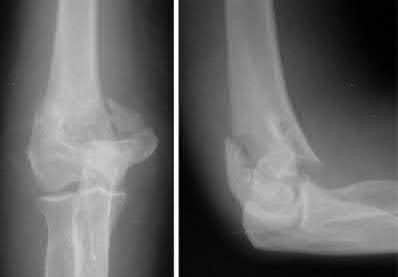

Figure A is an AP radiograph of a posterior knee dislocation. Figure B is a lateral showing the same injury.